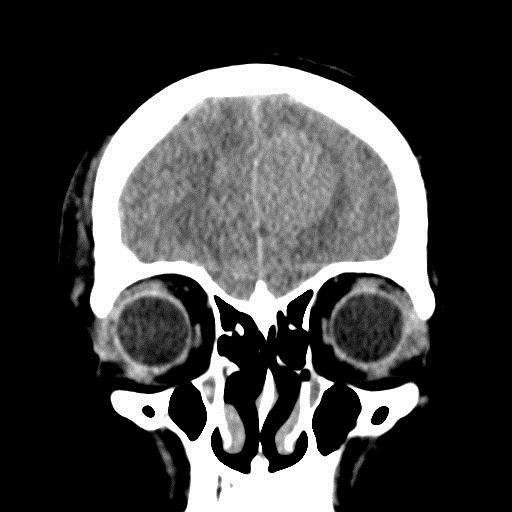

КТ головного мозга, кровоизлияние.

"Скорая" привезла женщину 75 лет, найденную на улице. На КТ направлена с д-зом: кома неясного происхождения. Вот такая картина на КТ.

Массивное медиальное кровоизлияние с прорывом в желудочки. Кровоизлияние в ствол. Признаки вклинения. В лбу может что-то и есть, но это не принципиально. А может быть и отечные извилины. Смущает, что нет масс-эффекта.

Про отек: субарахноидальных щелей совсем нет, по белому веществу и в стволе снижение плотности, извилины утолщены, серое вещество на этом фоне выглядит более светлым, толстым, подушкообразным.

Причина таких кровоизлияний, как правило, гипертензия и атеросклероз.